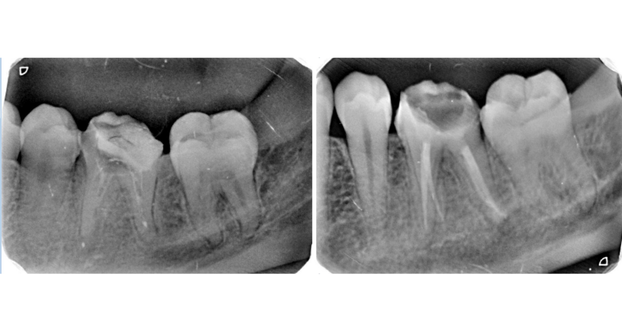

Quick Check + X-Ray

Root Canal

We look at your tooth and take a digital X-ray to see how deep the problem goes. If needed, local anesthesia is given to keep you comfortable.

Before And After